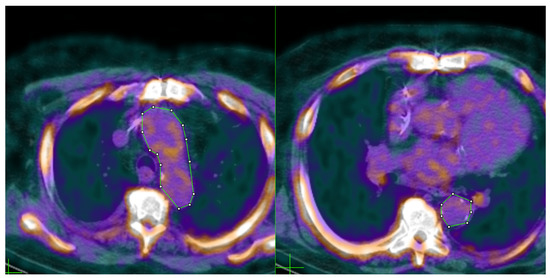

| Left | Right | |

|---|---|---|

| Age (years) | 68 | 71 |

| Weight (kg) | 100.2 | 99.3 |

| Height (m) | 1.83 | 1.77 |

| BMI (kg/m2) | 29.97 | 31.42 |

| 18F-NaF dose (mCi) | 9.8 | 10.4 |

| CRI-I | 3.08 | 4.74 |

| CRI-II | 1.65 | 3.31 |

| AC | 2.08 | 3.74 |

| AIP | 0.33 | 0.62 |

| HDL (mg/dL) | 51 | 35 |

| Aortic SUVmean | 1.285 | 1.495 |